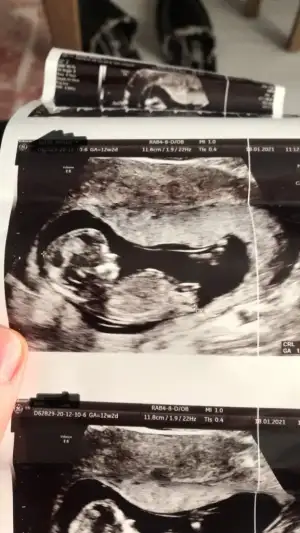

Ya saglikla gelsin oğlusunIkra meyra selamlar canım şimdi mesajımı bulamadım ama haber edeyim dedim. 6. Hafta kese için kız 12. Hafta nub için erkek demiştin. 12. Hafta tuttu

![]()

Erkek görünüyorAmin canım hepimizin12 haftalık usg resmi benimde